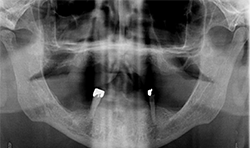

A 71-year-old male presented with a full maxillary denture and retained lower left canine and lower right first premolar (Fig. 3). He desired a semi-permanent solution to improve fit, function of upper and replace all missing teeth on the lower. An initial panoramic radiograph was taken for surgical and restorative planning purposes. The patient and doctor discussed options and it was decided a new maxillary full denture and a fixed hybrid prosthesis on the lower arch would be acceptable treatment options.

Fig.3

Fig.4

The patient’s medical history was evaluated for a mandibular fixed hybrid prosthesis using four Bicon implants and a TRINIA substructure. A CBCT revealed adequate bone for implantation and reviewed clinically after properly dissecting the mental nerve to avoid paresthesia. Four implants were placed through the anterior to increase the AP spread. Mandibular full thickness mucoperiosteal flap across the ridge was released and mental foramen were identified bilaterally. The posterior implant was placed 5 mm anterior to the mental foramen. All sites were prepared, checked for parallelism and enlarged to receive four implants each 4 mm x 8 mm with a 2.5 well (Fig. 4).